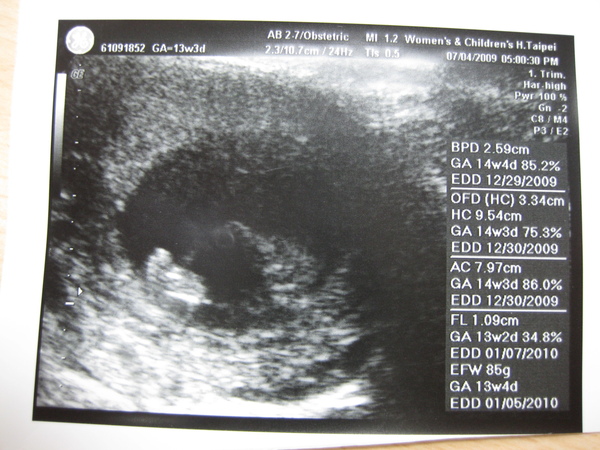

2009.07.04 婦幼醫院 頸部透明帶 14W_4D